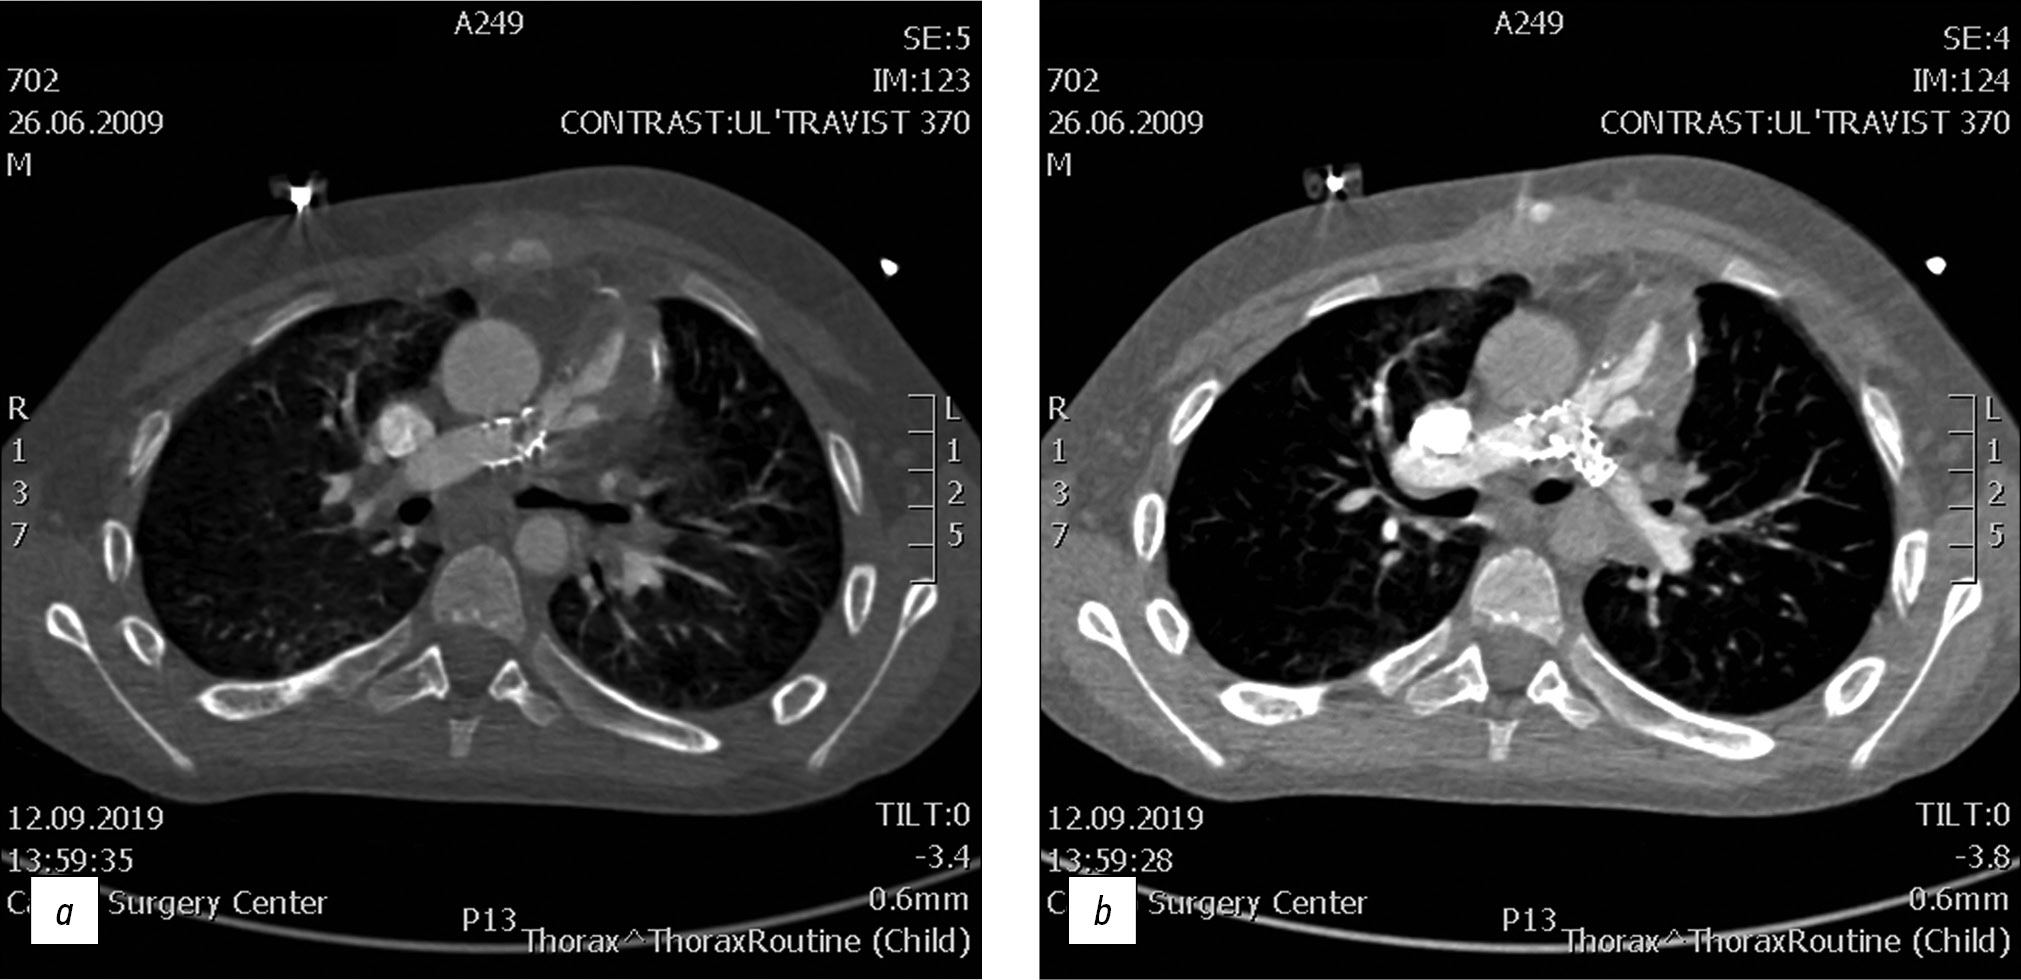

Fig. 1. CT of valve-containing conduit Contegra No. 16 and bilateral stents Palmaz Genesis XD 19-10.

A 12-year-old male with repaired tetralogy of Fallot, after implantation of valve-containing conduit Contegra No. 16 and bilateral stents Palmaz Genesis XD 19-10. Cardiac CT image clearly demonstrates thrombosis conduit. All the complications detected by CT were validated with angiography and were operated on.